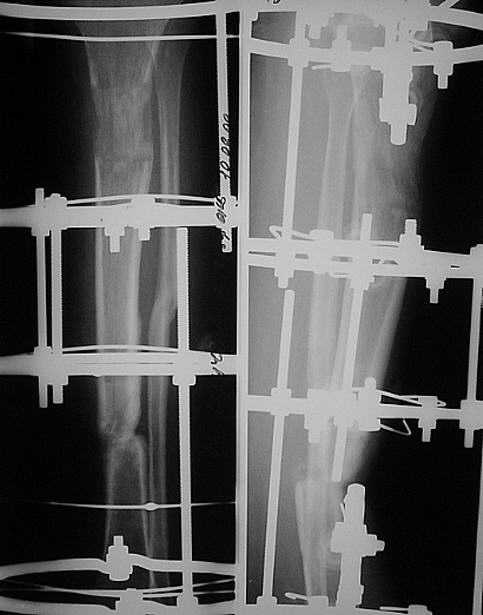

Уважаемые коллеги! Прошу совета. Больная, 32 лет, рабочая, 2,5 года

назад в ДТП получила открытый перелом костей левой голени в с/3. В

одной из больниц нашего города, где отдают предпочтение накостному

остеосинтезу, произведен остеосинтез б/б кости пластиной с 7

отверстиями с иммобилизаций гонитной гипсовой повязкой, почему-то с

эквинусной установкой стопы. В послеоперационном периоде наступил

некроз кожных покровов, нагноение раны, оголение кости и пластины на

протяжении 5 см. Следующие 7 месяцев идет борьба за сохранение

пластины, закрытие раны (кожная пластика).

Исход - несращение, остеомиелит, функционирующий свищ, миграция

винтов. Пластина удалена. И уже в другом лечебном учреждении,

произведена резекция концов б/б кости на протяжении 4,5 -5 см.,

гнойный процесс ликвидирован. Произведено успешное замещение дефекта

по Илизарову. Но при стыковке отломков возникла рекурвация голени до

25 град. Все эти годы стопа оставалась в эквинусном положении,

конечность не нагружалась. Имеется лимфедема, I cт. Движения в коленном суставе

восстановились, а в голеностопном остались на уровне качательных. К нам больная обратилась

На голени 4-х кольцевой аппарат: на дистальном и проксимальном

кольцах по 3 спицы, на средних - по одной. Аппарат стоит уже 7 мес.,

нестабилен,  мягкие ткани вокруг некоторых спиц воспалены. Продолжить

лечение имеющимся аппаратом вряд ли удастся.